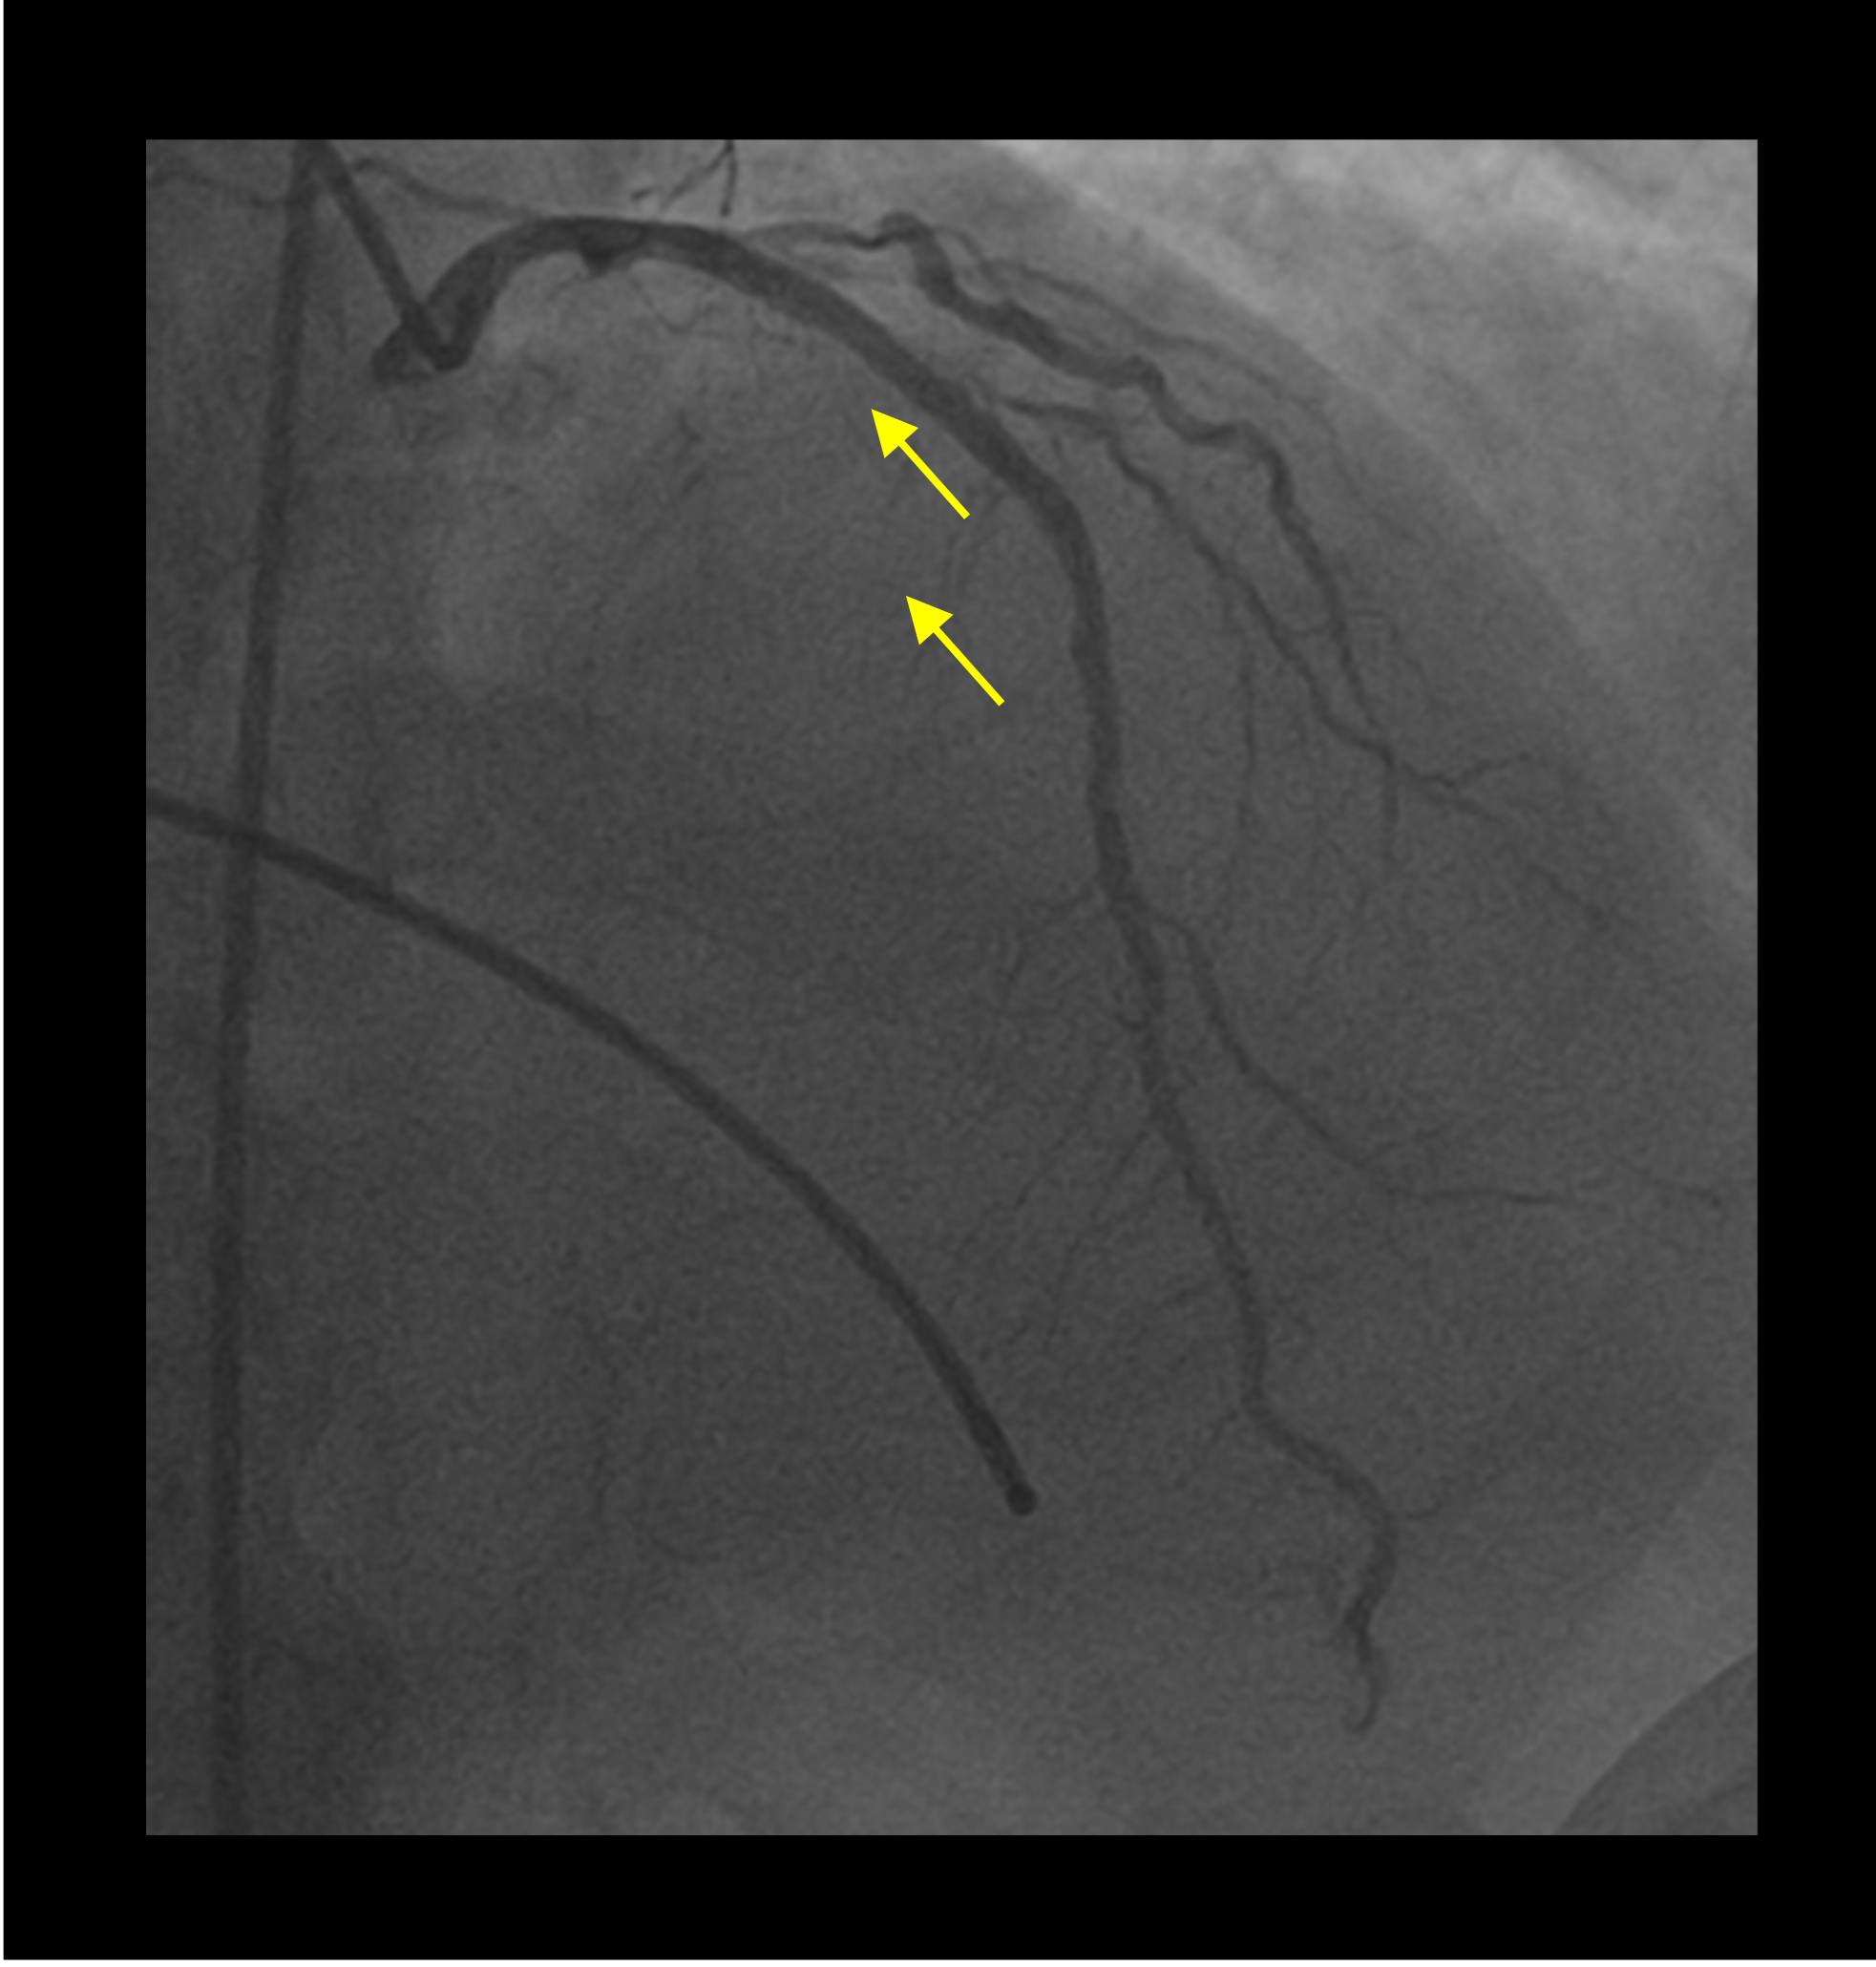

A 58-year-old man with a prior history of poorly controlled type 2 diabetes mellitus presented with a high-risk non-ST elevation myocardial infarction. Transthoracic echocardiography demonstrated a left ventricular ejection fraction of 51% with hypokinesia of the basal anteroseptal and anterior wall. An urgent coronary angiogram demonstrated diffuse calcific disease of the proximal to mid-segment of the left anterior descending (LAD) artery, with a bifurcation lesion at the level of the first diagonal branch (Medina 1,1,1). The left circumflex artery appeared chronically occluded, and a dominant right coronary artery (RCA) had tandem, tubular, angiographically significant lesions (Figure 1).